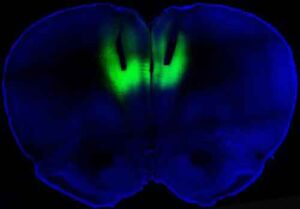

Un gruppo di scienziati americani, diretto dal Prof. Antonello Bonci del National Institute on Drug Abuse di Bethesda e stretto...